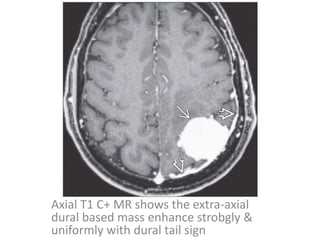

Axial T1 C+ MR shows the extra-axial

dural based mass enhance strobgly &

uniformly with dural tail sign

Axial T1 C+MR shows the extra-axial dural based mass enhance strobgly & uniformly with dural tail sign